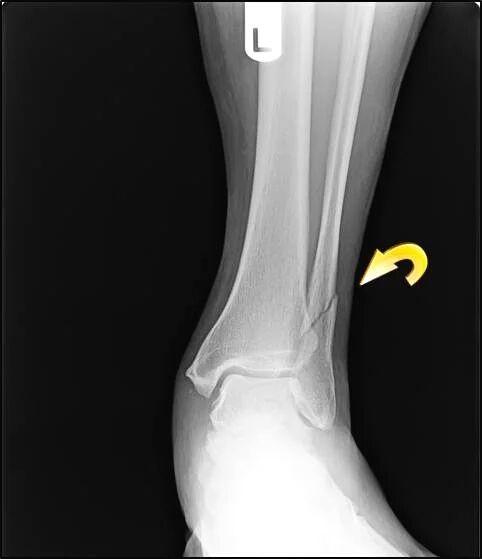

相关图片